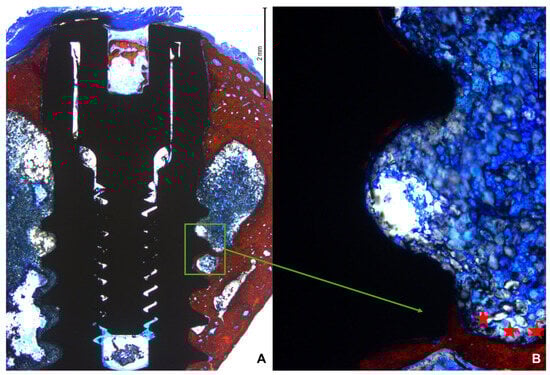

3.2. Descriptive Histological Evaluation

3.3. Histomorphometric Assessments